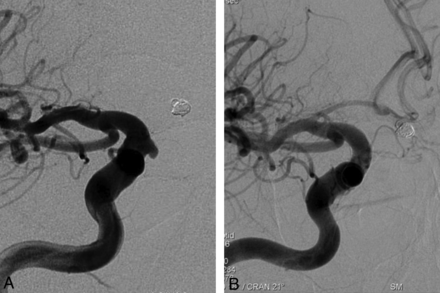

This retrospective study included 251 aneurysms treated with PEDs in 191 consecutive patients (mean age, 49.2 years; age range, 26–71 years; except for 1 pediatric patient who was 13 years of age) between November 2008 and September 2011. One hundred twenty-nine patients were female and 62 were male. Following ethics committee approval, 17 of the patients were included in the Pipeline for Uncoilable or Failed Aneurysms Study. Written informed consent was obtained from each patient. Sidewall aneurysms with wide necks (≥4 mm) or unfavorable dome-neck ratios (≤1.5) (Fig 1), large or giant aneurysms that might have or already had mass effect (Fig 2), fusiform aneurysms (Fig 3), blisterlike aneurysms (Fig 4), recurrent sidewall aneurysms, dissecting aneurysms (Fig 2), aneurysms at difficult angles to the parent artery (so that catheterization of the aneurysm and coiling may have increased risk) (Fig 5), and aneurysms in which a branch was originating directly from the sac (therefore endosaccular obliteration or clipping was likely to compromise the branch or result in a neck remnant) were treated with the PED (Figs 6 and 7). We intended to treat 1 patient with a giant, very wide-neck, cavernous ICA aneurysm presenting with mass effect symptoms by using a PED; however, we failed to bypass the neck of the aneurysm, resulting in treatment of the aneurysm with parent artery occlusion following a balloon occlusion test, without complications. This patient was not included in the study because a PED was not used. This was the only technical failure during the course of the series.

Preoperative 3D angiogram (A) shows a very wide-neck large ICA aneurysm. It could be reconstructed with several overlapping devices, creating a new vessel wall within the sac as seen on the perioperative DynaCT image (B). Postoperative CT obtained the same evening (C) reveals ipsilateral frontal intraparenchymal hemorrhage. 2D (D) and 3D (E) views of 6-month control angiography demonstrate the reconstruction of the parent artery and total occlusion of the aneurysm.

Two patients developed ipsilateral remote intraparenchymal hematomas. The first patient's hematoma developed within the first 8 hours after treatment (Fig 1). This hematoma was attributed to overmedication. The patient was placed on subcutaneous low-molecular-weight heparin despite her very high response to clopidogrel (the VerifyNow level was 97%) because the artery was reconstructed by using 16 devices overlapping in a telescopic fashion and we were worried about thromboembolic complications due to metal overload. The patient did not have any permanent neurologic sequelae from this event and was discharged home after 1 week. Control angiography showed total obliteration of the aneurysm with the parent artery reconstruction.